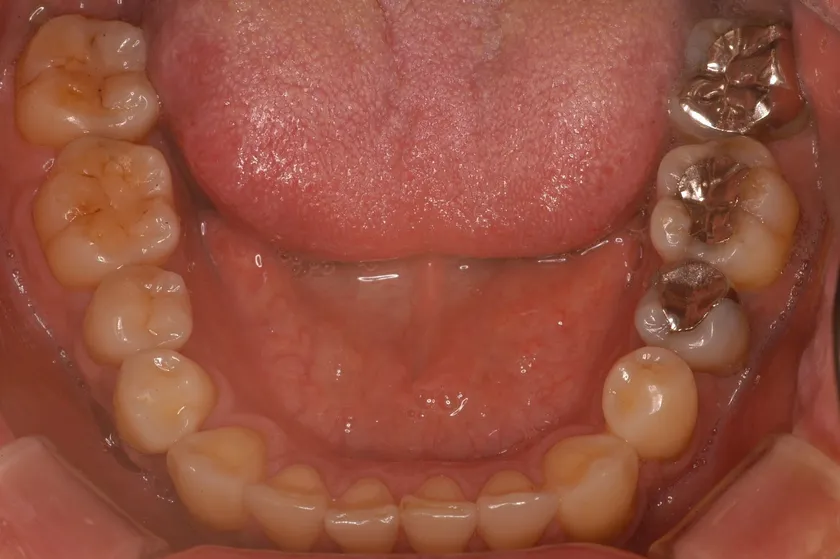

理想的な歯並び

「理想的な歯並び」と「現代人に多い歯並び」の画像、これは何を意味しているのか?

歯並びの中にあるもの。それは、「舌」だったのです。

歯並びが小さいと「舌が窮屈」になり、アゴの位置がずれてしまいます。